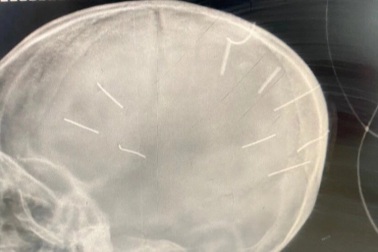

Cảnh sát hình sự Hà Nội điều tra vụ bé gái 3 tuổi nghi bị đinh cắm vào đầuCông an thành phố Hà Nội đã giao Phòng Cảnh sát hình sự điều tra, làm rõ vụ việc bé gái ở Canh Nậu, Thạch Thất có dị vật, nghi là đinh, cắm vào đầu.

Vụ bé gái 3 tuổi bị đóng đinh vào đầu: Từ "ác" không đủ diễn tả sự tàn độcSự việc bé gái 3 tuổi ở Hà Nội bị nhân tình của mẹ đóng cả nắm đinh vào đầu làm nhiều người nghẹt thở, bàng hoàng. Từ "ác" không đủ để nói về hành vi tàn độc với cháu bé.

Lãnh đạo Cục cảnh sát hình sự nói về vụ bé gái 3 tuổi bị đóng đinh vào đầuTheo ông Tô Cao Lanh, Phó Cục trưởng Cục cảnh sát hình sự, sau khi xảy ra vụ án bé gái 3 tuổi bị đóng 9 chiếc đinh vào đầu, đơn vị này đã chỉ đạo thu thập chứng cứ và bắt ngay các đối tượng liên quan.